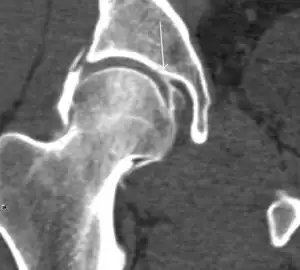

Synovial chondromatosis can be confidently diagnosed by X-ray when calcified cartilaginous chondromas are seen. However, other synovial proliferative processes, such as pigmented villonodular synovitis, require MRI for accurate diagnosis, although noncalcified synovitis can be suspected in radiographs by indirect signs, such as soft tissue swelling and/or erosions in the femoral head, femoral neck, or acetabulum (Figure 7).[1]

Figure 7:

Axial CT image of pigmented villonodular synovitis eroding the posterior cortex of the femoral neck.[1]

CT of synovial chondromatosis.[1]